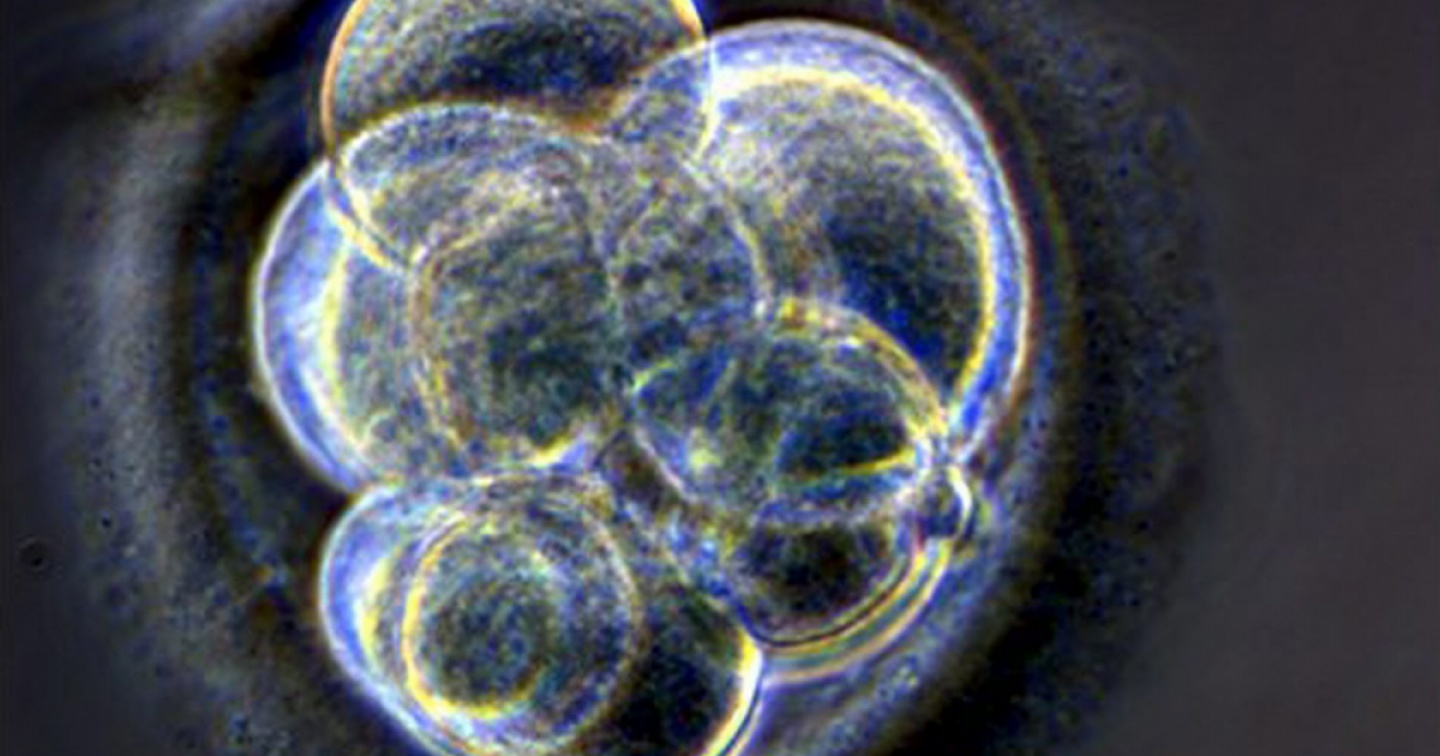

Ottenuto il primo embrione umano sintetico a partire da cellule staminali e quindi senza utilizzare ovociti e spermatozoi. Le cellule si sono aggregate spontaneamente, formando una struttura molto simile a un embrione umano, ma che non è in grado di completare lo sviluppo né di essere impiantato nell'utero. È invece uno straordinario laboratorio naturale per studiare lo sviluppo embrionale anche dopo i 14 giorni che oggi limitano la ricerca per motivi etici, capire la causa di aborti oggi inspiegabili, sperimentare farmaci e studiare malattie. Il risultato, non ancora pubblicato, è stato annunciato in apertura del convegno della Società internazionale per la ricerca sulle cellule staminali in corso a Boston da Magdalena Zernicka-Goetz, dell'Università britannica di Cambridge e del California Institute of Technology.

Da anni il suo gruppo sta studiando le tecnologie più efficaci nel guidare lo sviluppo delle cellule staminali e nell'agosto 2022 aveva ottenuto il primo embrione di topo sintetico con un cervello e cuore battente. "Possiamo ottenere modelli simili a embrioni umani riprogrammando cellule staminali embrionali", ha detto la ricercatrice a Boston, secondo quanto riferisce il quotidiano britannico The Guardian. La chiave è nella parola "modelli": quelli ottenuti a Cambridge "non sono embrioni umani e nemmeno si originano da cellule staminali prelevate da embrioni umani, ma sono strutture che hanno tessuti simili a quelli degli embrioni umani. Li potremmo definire strutture simili a embrioni, o embrioidi", ha osservato Amadei, che ha lavorato nel gruppo di Zernicka-Goetz a Cambridge e che recentemente è rientrato in Italia, all'Università di Padova.

Gli embrioni umani sintetici sono perciò aggregati di cellule staminali, indotte a svilupparsi in modo da poter dialogare fra loro e organizzarsi in modo spontaneo. "Le tecnologie che permettono di ottenere queste cellule sono disponibili da tempo e la novità è nel tipo di organizzazione ottenuta a Cambridge", ha aggiunto Amadei. Il grande vantaggio, secondo il ricercatore, sta nel fatto che gli embrioni sintetici sono "laboratori viventi per studiare lo sviluppo degli embrioni umani e il processo con cui si impiantano: su entrambi questi aspetti sappiamo poco per i limiti etici che ci diamo come ricercatori". Grazie agli embrioidi sarebbe possibile, per esempio, capire perché molte gravidanze falliscano, comprendere meglio le malattie genetiche a partire dalle anomalie rilevabili negli embrioni, o ancora sperimentare farmaci per capire se le donne in gravidanza possano assumerli senza rischi per l'embrione. Avere a disposizione questi embrioidi significherebbe avere "una piattaforma sintetica per testare la tossicità di farmaci o per verificarne il meccanismo d'azione con un dettaglio a livello molecolare".